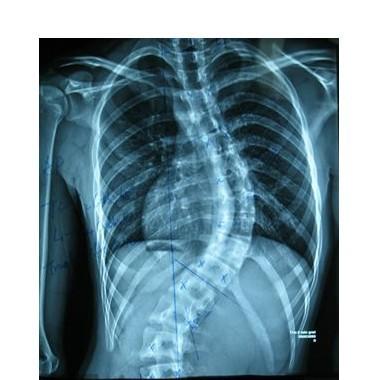

QZ16030094 姓名:陈先生 性别:男 年龄:32岁

- 病情

AS ①晚期 ②重度 病史:5年+

- 治疗

治疗后骶髂关节疼痛消失,腰椎前屈、背伸侧弯活动自如,膝关节无压痛感,复查血沉、C反应蛋白、等各项检查均已达到临床康复的标准。